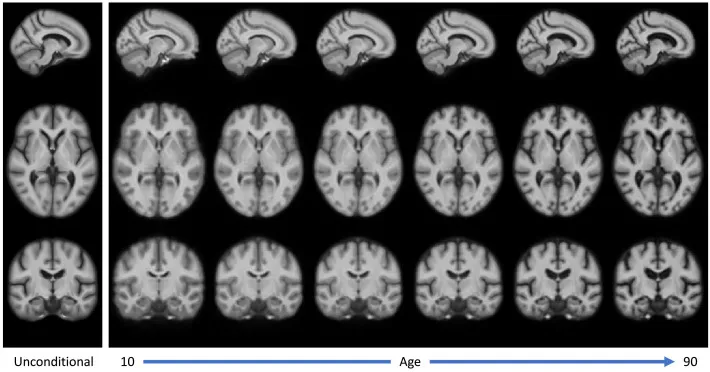

图1.AtlasMorph开发的条件模板,作为年龄的函数。

图5.通过AtlasMorph获得的强度模板。左图:无条件强度模板。右图:从我们学习到的模板函数中抽样得到的年龄从10岁到90岁的条件强度模板,从左到右。条件模板捕捉到了年龄相关的萎缩的已知迹象,如在图12中分析。

图6.通过AtlasMorph获得的标签图模板。左图:无条件标签图模板。右图:条件标签图。从我们学习到的模板函数中抽样得到的年龄从10岁到90岁的模板,从左到右。标签图的可视化是通过为每个类别分配最高概率的标签获得的。条件模板捕捉到了年龄相关的萎缩的已知迹象。

研究结果显示,AtlasMorph生成的模板明显比简单平均法获得的模板更清晰。条件模板成功捕捉了与年龄相关的萎缩现象,如脑室增大和海马体缩小,这与已知的群体趋势一致。在配准性能方面,AtlasMorph模型在Dice评分和表面距离上持续优于所有基线方法,包括ANTs和Aladdin变体。联合学习标签图与强度模板显著提高了性能,且条件变体略优于无条件变体。尽管年轻受试者的分割结果相对较差,可能与数据不平衡有关,但AtlasMorph在所有年龄段均表现最佳。变形场规则性良好,雅可比行列式的负值数量微不足道,表明其具有解剖学上的合理性。新的中心性损失公式使AtlasMorph比LT2019模型更能准确捕捉群体趋势,这在脑室和海马体体积分析中得到证实。此外,使用100个受试者平均值进行初始化比单个随机受试者初始化能获得更稳定、更优异的结果。AtlasMorph还成功学习了结合认知障碍(AD、MCI、CN)等额外属性的模板。